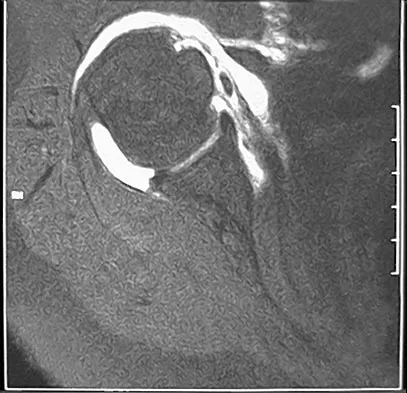

خلع الركبة هو إصابة خطيرة تتضمن انفصال مفصل الركبة، ويتطلب تقييمًا فوريًا وعلاجًا دقيقًا للحفاظ على الأطراف. يشمل العلاج عادة الرد الفوري، تقييم الأوعية الدموية والأعصاب، ثم الجراحة لإعادة بناء الأربطة المتضررة، يتبعها برنامج تأهيل مكثف لاستعادة الوظيفة.

الخلاصة الطبية السريعة: خلع الركبة هو إصابة خطيرة تتضمن انفصال مفصل الركبة، ويتطلب تقييمًا فوريًا وعلاجًا دقيقًا للحفاظ على الأطراف. يشمل العلاج عادة الرد الفوري، تقييم الأوعية الدموية والأعصاب، ثم الجراحة لإعادة بناء الأربطة المتضررة، يتبعها برنامج تأهيل مكثف لاستعادة الوظيفة.

يُعد خلع الركبة من أخطر الإصابات التي قد تصيب مفصل الركبة، فهو يمثل انفصالًا كاملًا بين عظم الفخذ وعظم الساق (الظنبوب). هذه الإصابة لا تقتصر على الأربطة فحسب، بل غالبًا ما تتسبب في أضرار متعددة للأنسجة المحيطة، بما في ذلك الأوعية الدموية والأعصاب، مما يجعلها حالة طارئة تهدد الطرف المصاب. على الرغم من أنها تُعتبر إصابة نادرة نسبيًا، إلا أن تقدير حدوثها قد يكون أقل من الواقع بسبب ميل الركبة للعودة إلى مكانها تلقائيًا قبل وصول المريض إلى المستشفى.

تُعد إدارة خلع الركبة جراحية في الغالب، نظرًا للتمزق الشديد في الأنسجة الرخوة واحتمال كبير لعدم الاستقرار طويل الأمد والعجز الوظيفي. يُعد التقييم الأولي والرد وتثبيت الأوعية الدموية والأعصاب من الأولويات الحادة. عادة ما يتم اتخاذ قرار العلاج الجراحي النهائي مقابل العلاج غير الجراحي بعد معالجة المشكلات الحادة التي تهدد الطرف وإكمال تقييم شامل للإصابة (بما في ذلك التصوير بالرنين المغناطيسي).